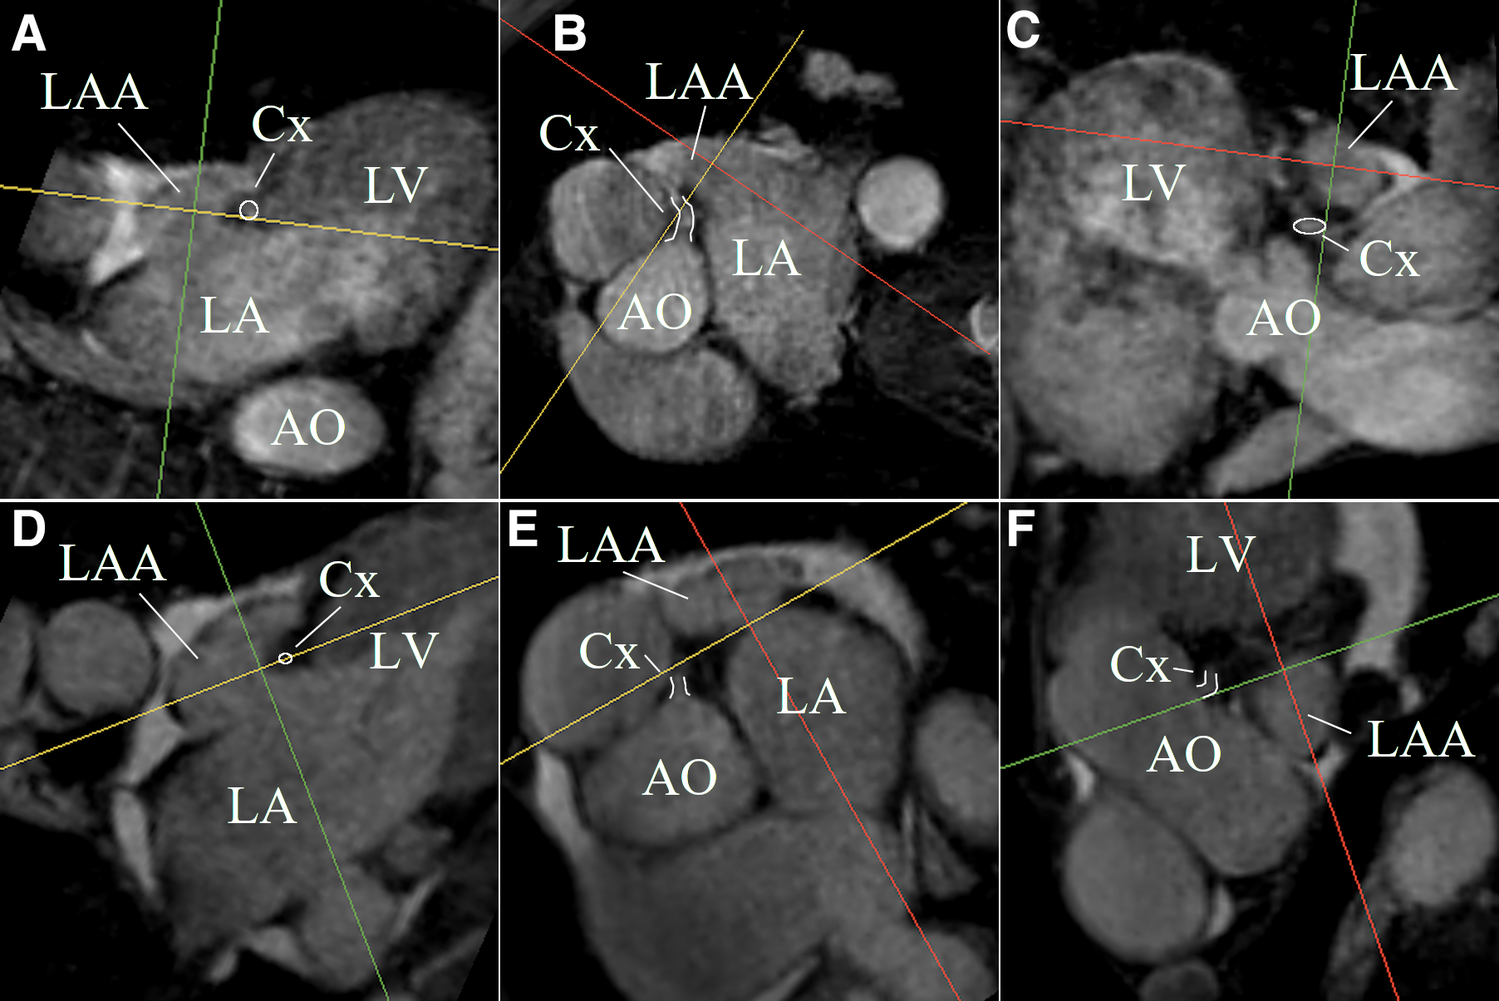

The LAA could be identified, segmented, and measured on the non-contrast-enhanced CMR despite severe arrhythmia in all patient data sets. Figure 4 shows MPR views of two LAA anatomies exemplifying the ability of non-contrast-enhanced CMR to identify the LAA anatomy and the landing zone marker Cx. The acquisition duration was depending on the heart rate, arrhythmia rejection, and respiration navigator efficiency but could be kept below 15 min in all cases.

Figure 4

MPR views of two LAA anatomies (first anatomy (A–C); second anatomy (D–F)) exemplifying the ability of non-contrast-enhanced CMR to identify the LAA anatomy and the landing zone marker Cx (white highlighted).